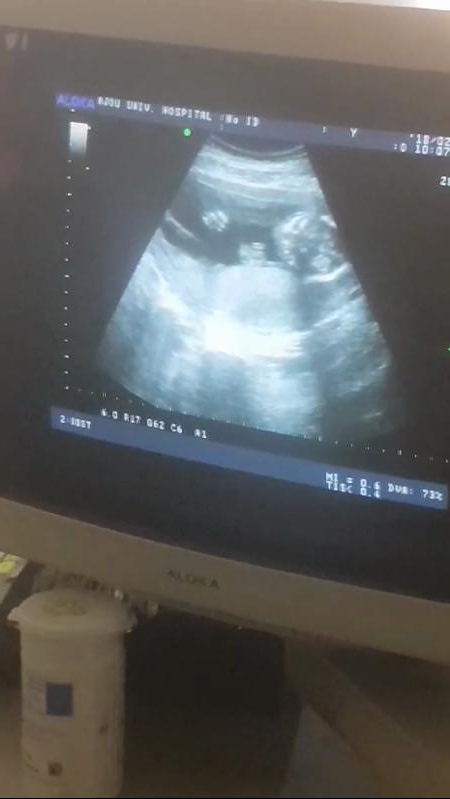

임신 부종 그리고 무서운 임신중독증 기록 : 2018. 5. 2 2018. 5. 2 만복 28주 1일이날은 비가 부슬부슬 내...